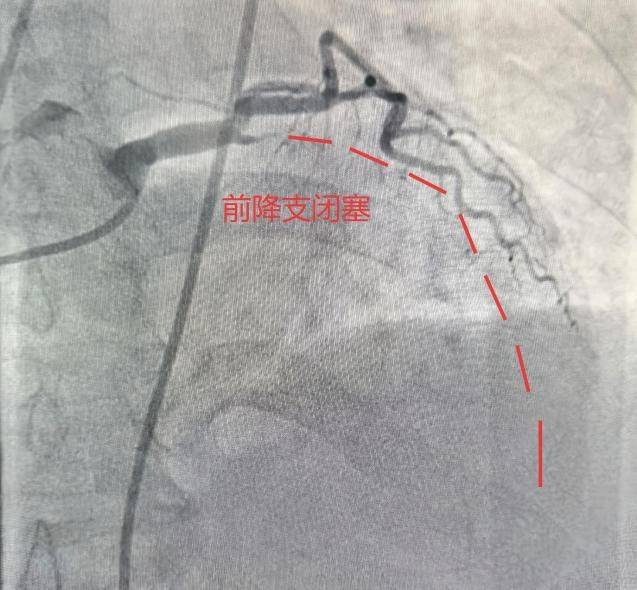

合肥市第三(san)群众医院心血管内科副主任医师樊(fan)宗成向908新媒体讲述了当时的细节(jie)。急救职员(yuan)测血抬高,做心电图(tu)提醒:急性遍及前壁心肌(ji)梗死!120通(tong)过胸痛中心绿色通(tong)道将(jiang)她间接被送入导管室,冠(guan)脉造影(ying)显示,她的前降支(心脏最重要(yao)的血管之一)已经完全闭塞(sai)。植入支架、开(kai)通(tong)血管……经由近40分钟的抢救,她终究转危为(wei)安。周阿姨怎(zen)么也想不(bu)通(tong):最冷的冬天感冒都没有,反(fan)而正在春暖花开(kai)的3月住进了医院?这就(jiu)是春天,一个万物复苏,却(que)也暗(an)藏“心”机(ji)的季候。